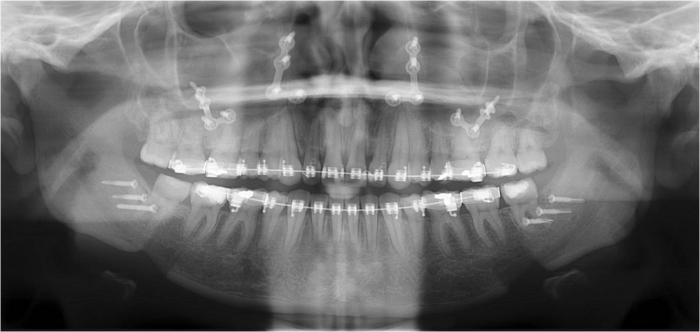

Raio x inicial

Raio x após a cirurgia